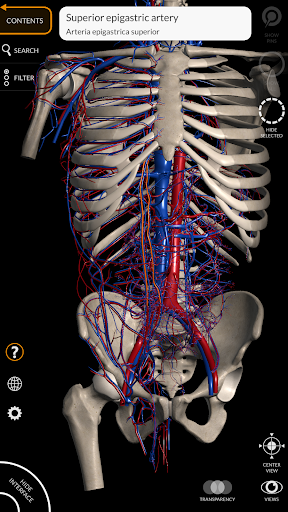

"Anatomy 3D Atlas" дозволяє легко та інтерактивно вивчати анатомію людини.

Завдяки простому та інтуїтивно зрозумілому інтерфейсу можна спостерігати кожну анатомічну структуру під будь-яким кутом.

Анатомічні 3D-моделі особливо деталізовані та мають текстури з роздільною здатністю до 4k.

• Серцево-судинна система

• Вибравши модель або шпильку, з’явиться відповідний анатомічний термін